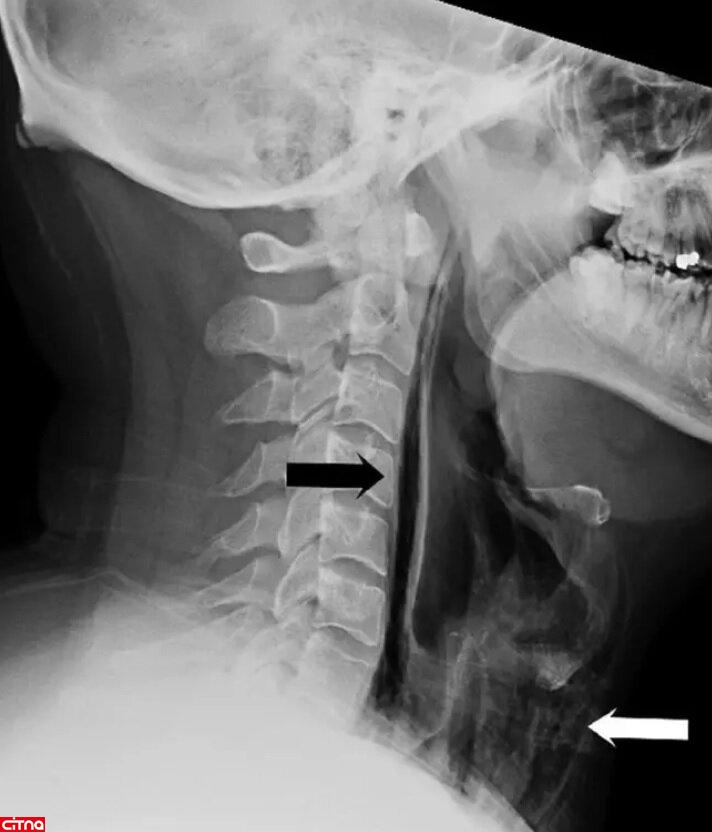

در بیمارستان وقتی از گلوی این مرد تصویربرداری شد، پزشکان ابتدا تورم و سپس رگه‌هایی از هوا در میان بافت گلوی او مشاهده کردند. این رگه‌های هوا که به‌صورت حباب‌های بسیار ریزی دیده می‌شدند، نشان می‌داد که گلویش دچار پارگی شده است.